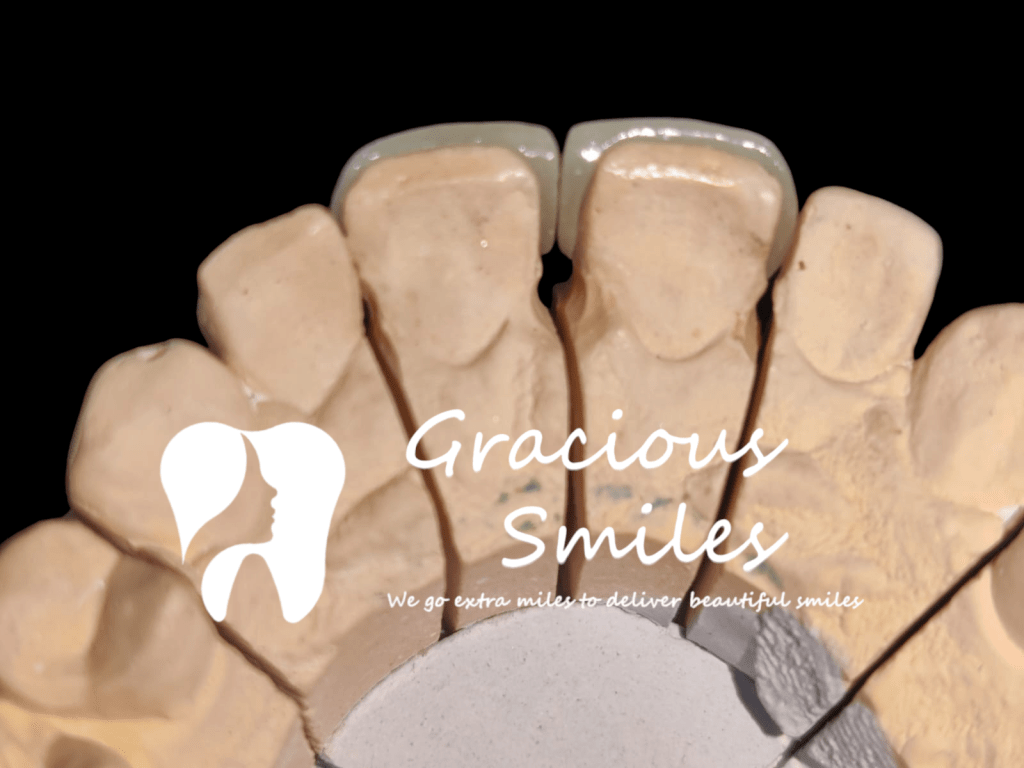

Ceramic Veneers